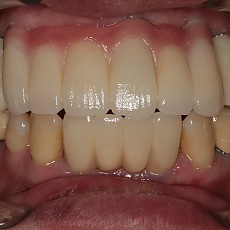

시술전후사진 2 페이지

Total 62건 2 페이지